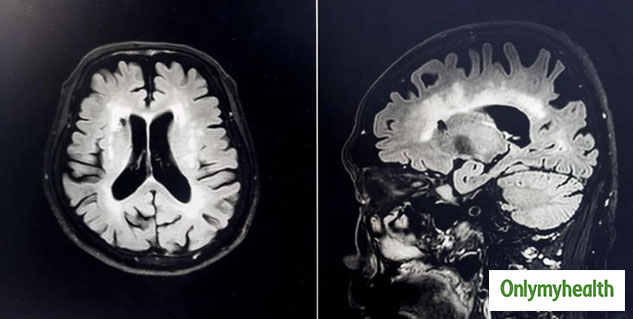

कमजोर याददाश्त और चीजों को भूल जाना अक्सर अल्जाइमर के संभावित लक्षण होते हैं। यह लोकप्रिय धारणा के विपरीत, अल्जाइमर न केवल पुराने या वृद्ध लोगों में होता है, बल्कि यह किसी भी उम्र के किसी भी व्यक्ति में हो सकता है। यह एक न्यूरोलॉजिकल समस्या है और अफसोस की बात तो यह है कि यह रोग अनुपचारित है। हालांकि, यह रोकथाम करने योग्य है। जी हां, आप स्वस्थ खानपान और मन को पर्याप्त आराम देकर अल्जाइमर और डिमेंशिया जैसी बीमारियों के जोखिम को भी कम कर सकते हैं। अल्जाइमर या डिमेंशिया जैसी न्यूरोलॉजिकल समस्याओं से बचने के लिए एक र्प्याप्त नींद लेना बहुत जरूरी है। एक अच्छी नींद आपके मन और शरीर, दोनों के लिए बहुत जरूरी है। यदि आप ठीक से नहीं सोते हैं, तो आप अल्जाइमर सहित कई स्वास्थ्य समस्याओं के शिकार हो सकते हैं। यही वजह है कि डॉक्टर भी नींद के महत्व के बारे में बात करते हैं और इस पर जोर देते हैं। वहीं हाल में अब वैज्ञानिकों ने एक ऐसा तरीका खोज लिया है, जहां नींद के पैटर्न का विश्लेषण करने से अल्जाइमर की संभावना का अनुमान लगाया जा सकता है। आइए इस बारे में विस्तार से जानने के लिए इस हालिया शोध को पढ़ें।

पत्रिका 'करंट बायोलॉजी' ने हाल ही में एक अध्ययन प्रकाशित किया है, जिसमें पाया गया है कि कैसे न्यूरोसाइंटिस्ट अल्जाइमर के जोखिम का अनुमान लगा सकते हैं। किसी व्यक्ति के स्लीप पैटर्न का विश्लेषण करके, अल्जाइमर की संभावना विकसित होने का अनुमान लगाया जा सकता है। वैज्ञानिकों के अनुसार, डिमेंशिया और अल्जाइमर को रोकने के लिए गहरी, अच्छी और र्प्याप्त नींद लेना महत्वपूर्ण है।

इस शोध के लिए, वैज्ञानिकों ने 32 स्वस्थ वृद्ध वयस्कों को लिया और उनकी नींद की गुणवत्ता का अध्ययन किया। उन्होंने नींद की गुणवत्ता को 'बीटा-एमाइलॉयड' के साथ मिलाया, जो एक है विषाक्त प्लाक है, जो अल्जाइमर का कारण बनती है। यह प्लाक तंत्रिका मार्गों और संज्ञानात्मक कार्यों को प्रभावित करती है, जिससे व्यक्ति अपनी याददाश्त खो देता है। इसके अलावा, अल्जाइमर के मरीज डिप्रेशन से भी पीड़ित होते हैं।